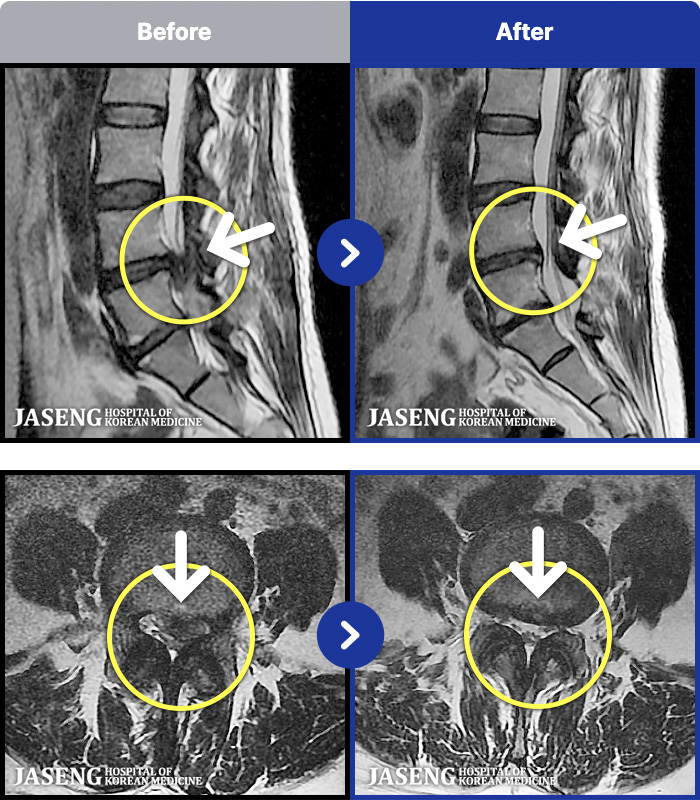

[ϻ] 24.07.25~25.08.01

ȯںп Ǹ ǿ ԿǾ, ο ġ ۿ Ƿ ġḦ Ͻñ ٶϴ.